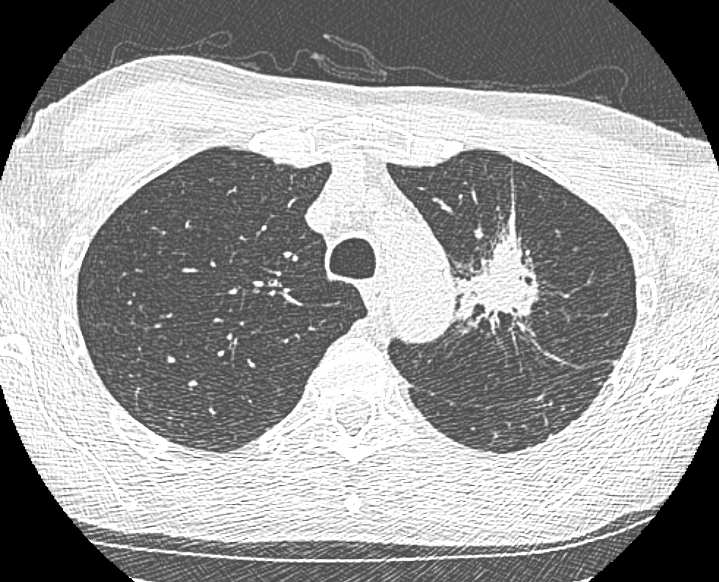

Ramsy Abdelghani, MD@Rabdelgh·

Cool case: 4.5mm partially solid PET-Avid LLL nodule. Used High PEEP/Tidal volume and wedged left side up to decrease dependent atelectasis. Navigated with Ion and adjusted with Philips CBCT. ROSE positive for Adenocarcinoma. Exciting times in lung cancer care! #ION #cbct